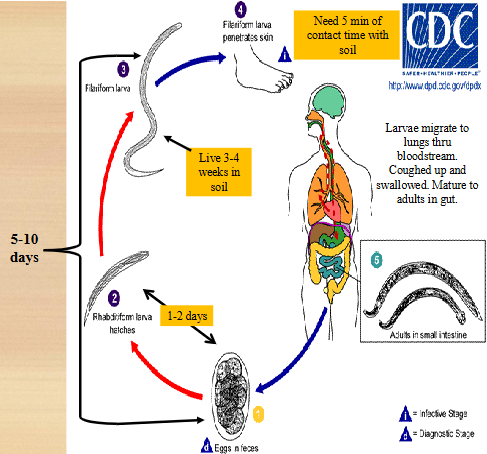

hookworm life cycle

unembryonated eggs are passed in feces

develop into rhabditiform larvae (1-2 days)

rhabditiform → filariform larva (lives 3-4 weeks in soil)

filariform penetrates skin of definitive host

larvae migrate to lungs; coughed up and swallowed

mature into adults in gut

adults live in small intestine

symptoms of hookworm infection

Itching at site of skin penetration & edema

Filariform larvae penetrate skin

Pulmonary symptoms once they reach the lungs

Eosinophilia seen

GI stage:

Chronic blood loss causing IDA--worms ingest blood

Protein malnutrition

Growth and mental retardation with lethargy

hookworm disease

Pathogenesis & degree of anemia is directly related to worm burden

Worm produces anticoagulant--enhances bleeding